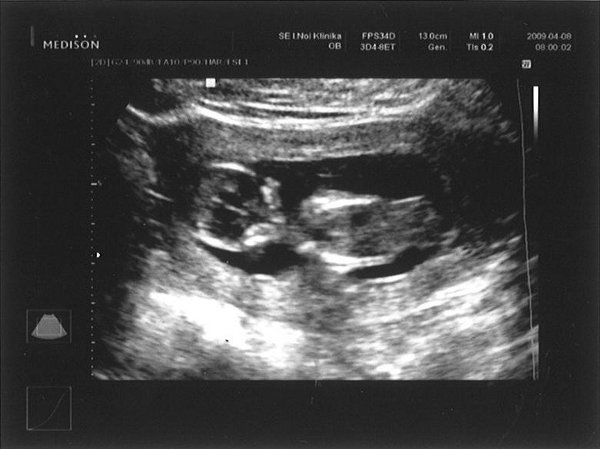

Mi ma reggel voltunk genetikán... Nyaki redő és gerinc rendben, szivecske a helyén dobog, hallottuk is a szívverését, kaptunk 3 percnyi videofilmanyagot és egy képet is. Minden rendben van a picivel. 58 mm-es már a drágám.NAgyon ugra-bugrált és integetett nekünk.... szóval teljesen el vagyok olvadva tőle :lol: :lol: :lol: :lol: :lol: :lol:

És a sztárfotónk:

Kép